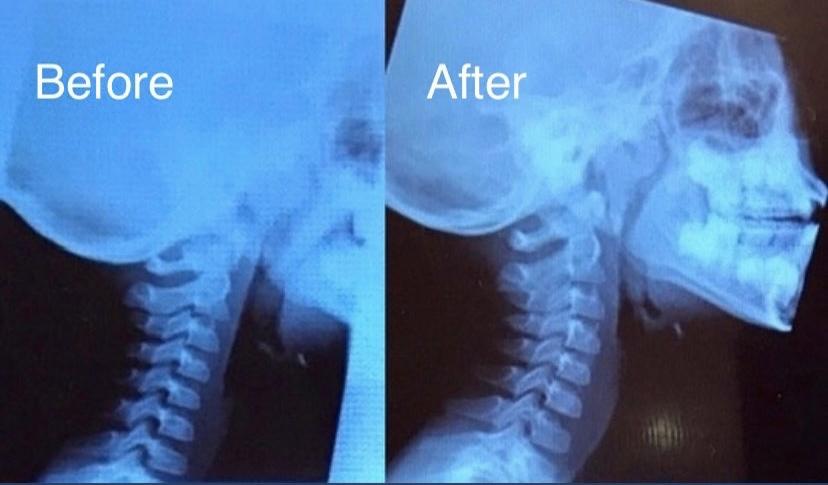

ストレートネックの改善例(小学生の男の子)

最近特に多く見受けられるようになったストレートネック、現代ではスマホやパソコンなどの使用頻度が増えてきたことも関係あってか、大人だけではなく子供にも多くなってきているように思います。見た目だけ、外見だけによる姿勢変化だけではなく、レントゲン画像における内部からの確かなストレートネックの改善により首の痛みや肩こりなどが大幅に改善されたようです。

※これは個人の感想と画像の結果であり施術の効果を保障するものではありません。また効果には個人差があります。